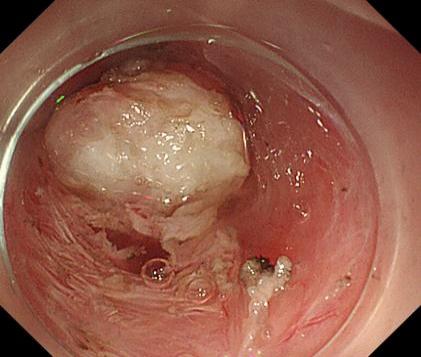

50f14f57e31f4fcb8cc67db07e7637a3.Jpeg5a155f6b9d364f049bf504276762fa4e.Jpegae69de3d0b564c66bdf2294699da75a6.Jpeg

胃底間質(zhì)瘤                內(nèi)鏡下全層切除術(shù)后創(chuàng)面         切除后標(biāo)本

內(nèi)鏡下全層切除術(shù)(EFTR):治療消化道黏膜下腫瘤(最主要):起源于固有肌層深層、部分腔外生長(zhǎng)、與漿膜層密不可分;少部分抬舉征陰性消化道癌前病變和早期癌;少部分困難解剖部位結(jié)腸病變(如結(jié)腸憩室內(nèi)腺瘤)等。